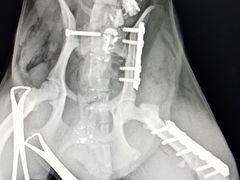

• 思宇宠物医院

• -思宇宠物医院

金木世纪公园店 | 20-05-16